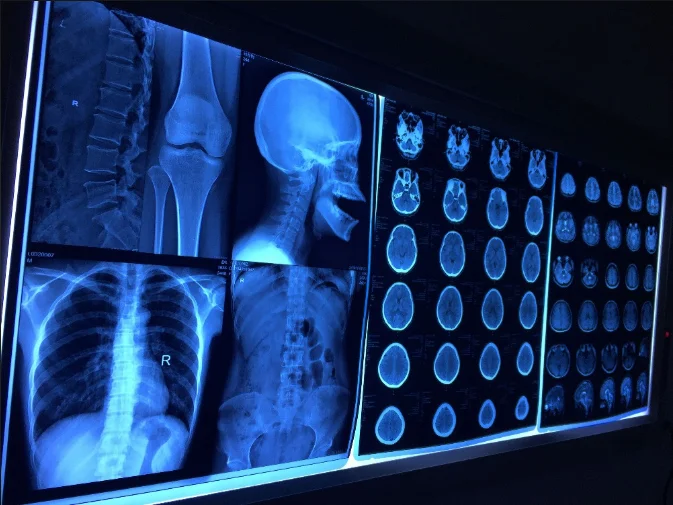

Лазерная камера сетевая для печати изображений на пленке стандарт dicom